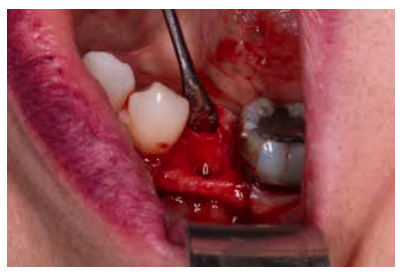

Materials and methods: A study was carried out on 6 patients from the Faculty of Dentistry of the Complutense University of Madrid performing the technique of alveolar ridge preservation. Two groups were established, a test group in which the alveolar socket was filled with calcium phosphate and added silicon and a control group where the socket was filled with bovine hydroxyapatite. After 3 months, a cone-beam computed tomography was performed to evaluate the bone density achieved by both biomaterials.

Andrés-Veiga et al,7 observed that this amount of bone resorption can vary between one individual and another and even in the same individual at different times of life, due to the influence of a series of local and systemic factors. Post-extraction alveolar ridge preservation (PAP) is a surgical technique aimed at reducing the collapse of the alveolar ridge after tooth extraction with a biomaterial, to facilitate subsequent implant rehabilitation8-10.